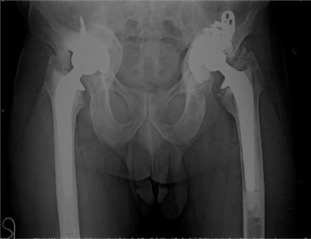

There were 61 patients (50 male, 11 female) with 105 affected hips (72% bilateral, 28% unilateral). The average patient age at surgery was 41.3 ± 10.2 years old. The age of patients at THA was as follows: <30 years for 14 patients (23 hips), 31–50 years for 41 patients (73 hips) and >50 years for 6 patients (9 hips) (Graph 1 ). The younger age at diagnosis (<30 years old) of AS was correlated with younger age at THA (p < 0.05). Bone ankylosis was detected in 37 (35%) and acetabular protrusion was noticed in 18 (17%) hips in pre-operative radiographs (Fig. 1 , Fig. 2 , Fig. 3 ; Fig. 4 ) (Table 1 ). The mean pre-operative flexion contracture was 20.3°±21.8°. In patients without ankylosis, the mean total hip range of motion (ROM) was 67.8°±25.7°.

Fig. 2. Four years after bilateral simultaneous THA. |